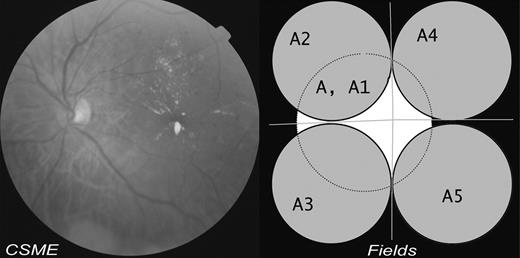

The single nonsimultaneous stereoscopic pair of central images were acquired manually by horizontal translation of the fundus camera and labeled as A and A1. Four equidistant images covering the peripheral areas of the retina were also taken (Fig. 1) and were labeled A2, A3, A4, and A5, respectively. A and A1 are 45° fields, focused centrally between the temporal margin of the optic disc and the center of the macula, with the horizontal central line of the image passing through the center of the disc. Stereoscopic images are obtained by shifting the camera laterally; a slight delay between the first and the second image may be necessary to allow for adequate pupil mydriasis. A2 is a 45° field superotemporal to the optic disc so that the lower edge of the field is at a tangent to the horizontal line passing through the center of the optic disc and the nasal edge of the field is at a tangent to the vertical line passing through the center of the disc. Similar fields in the inferotemporal (A3), superonasal (A4), and inferonasal (A5) quadrants were imaged.

Stereo-photograph pair and four peripheral fields of ADRES 3.0 five 45° field protocol with a sample image.